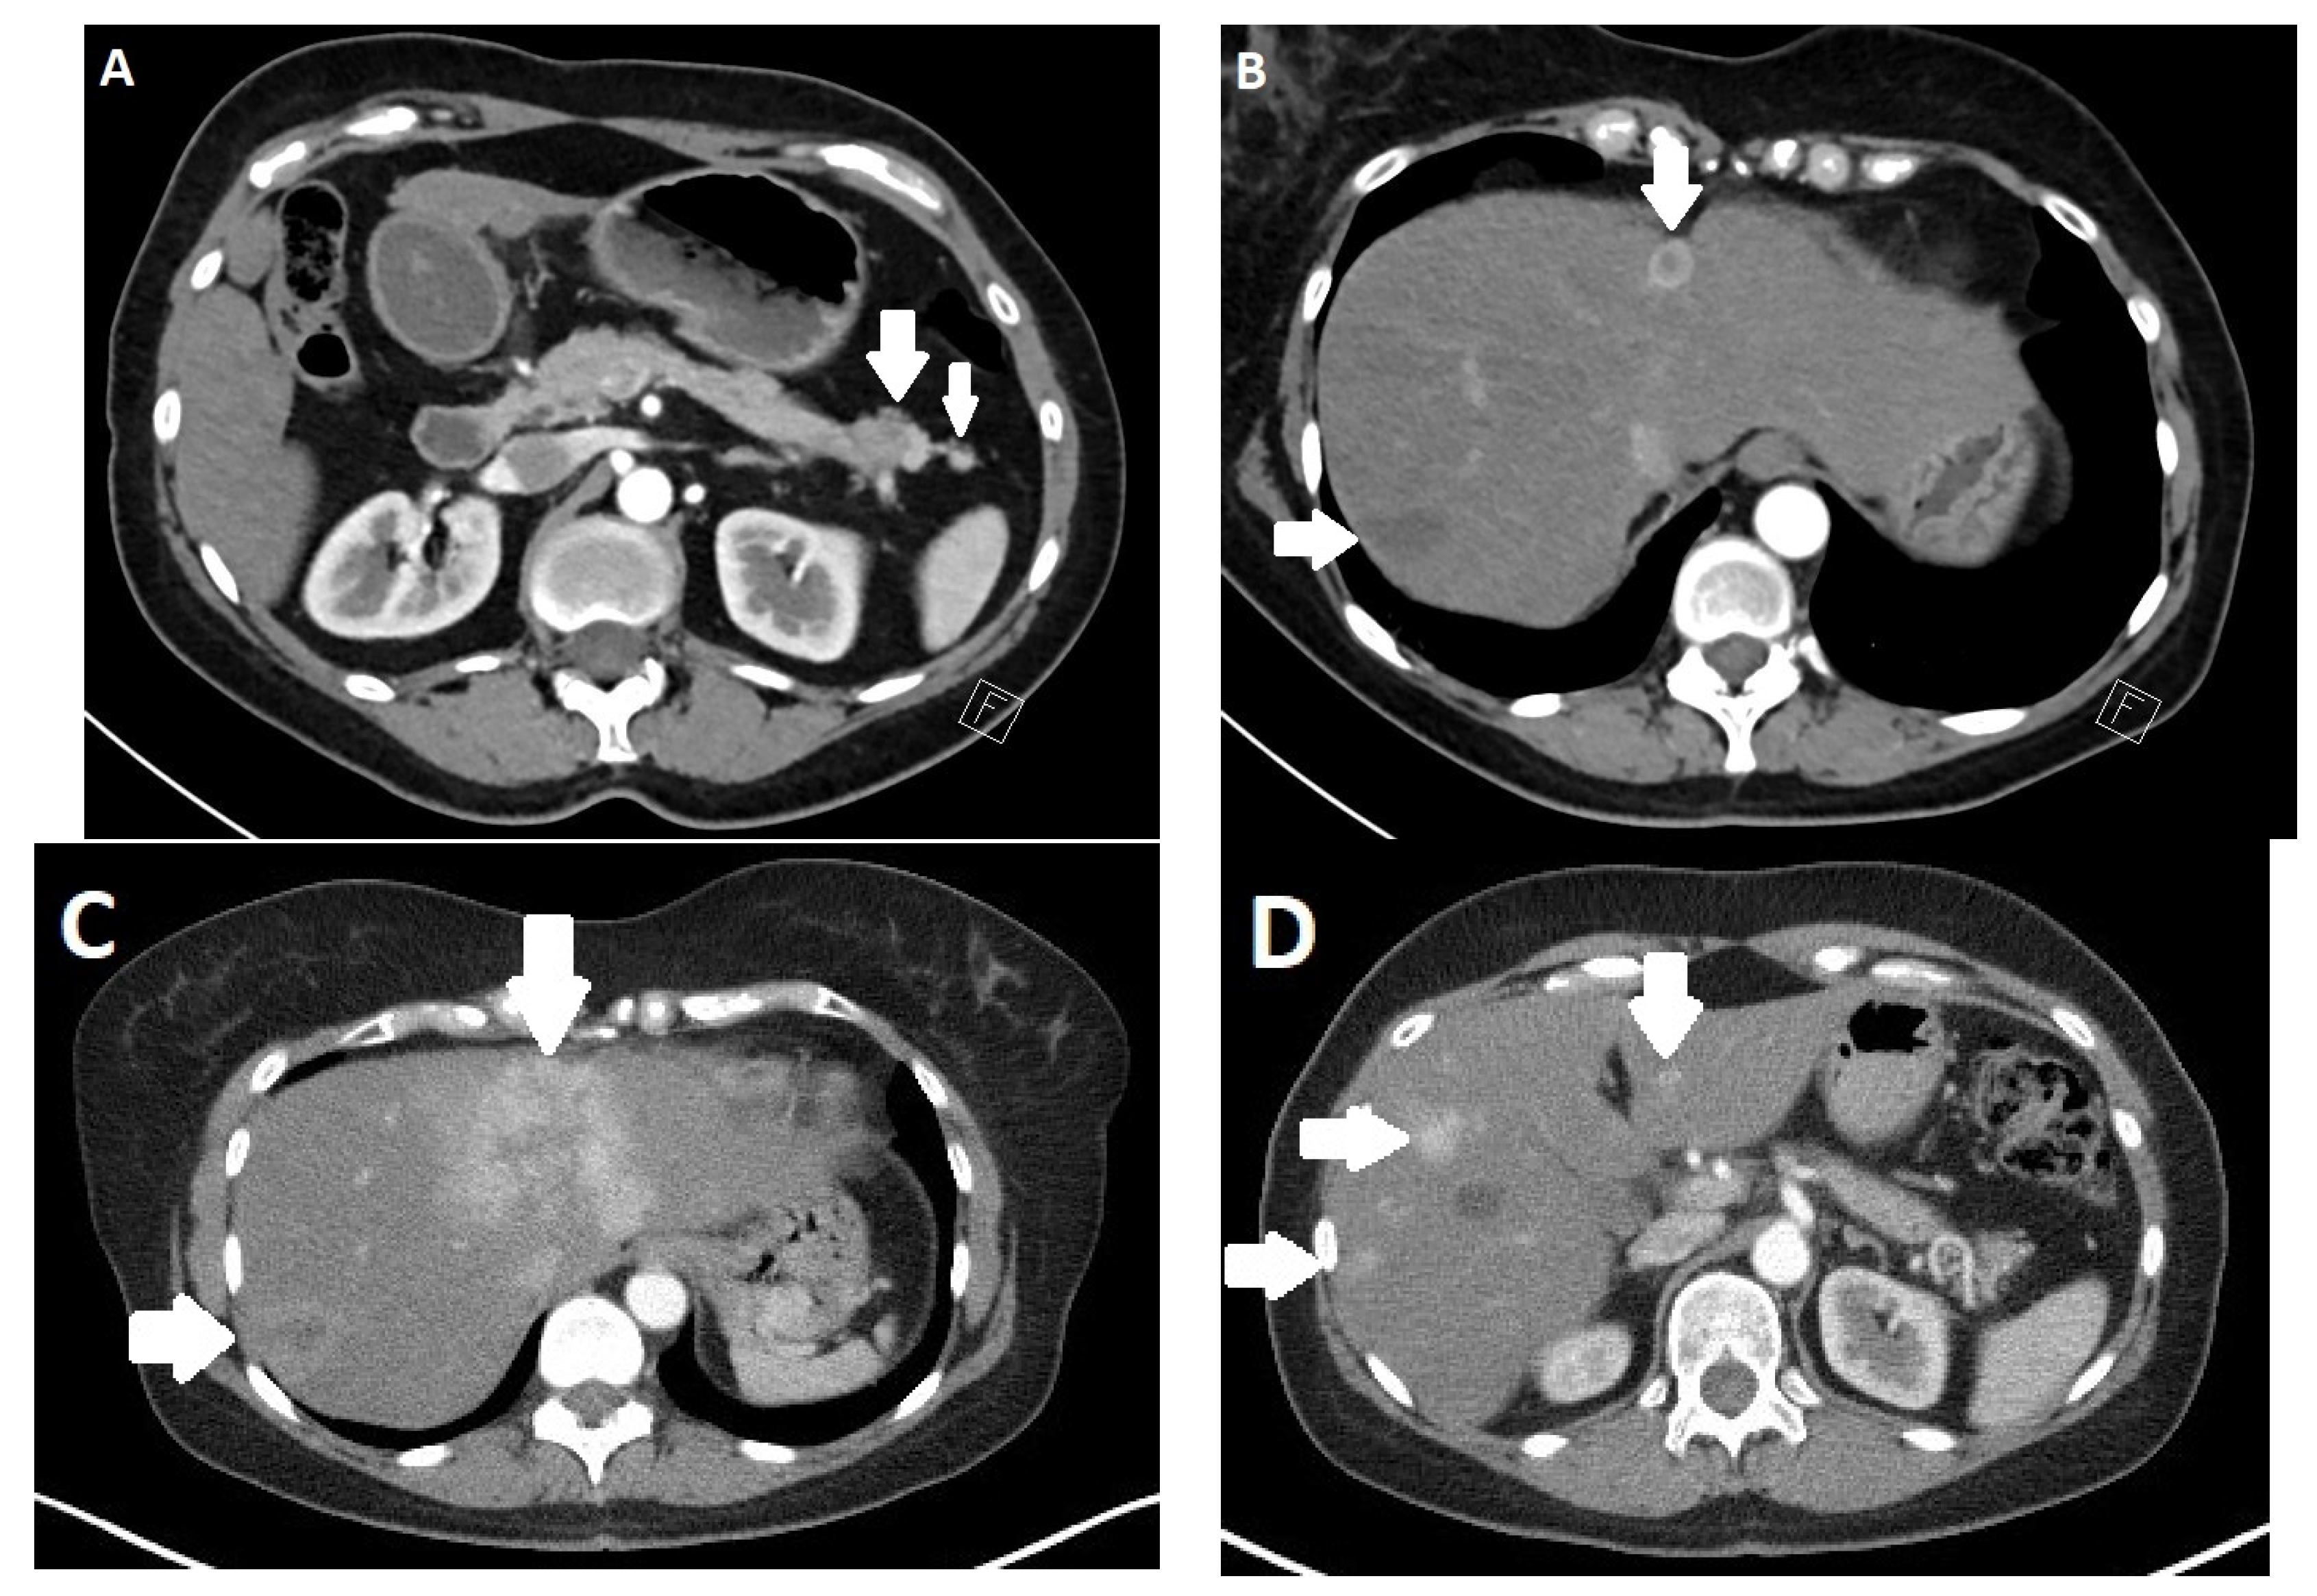

3.4. Imaging

- Kim, J.H.; Eun, H.W.; Kim, Y.J.; Lee, J.M.; Han, J.K.; Choi, B.I. Pancreatic neuroendocrine tumour (PNET): Staging accuracy of MDCT and its diagnostic performance for the differentiation of PNET with uncommon CT findings from pancreatic adenocarcinoma. Eur. Radiol. 2016, 26, 1338–1347. [Google Scholar] [CrossRef] [PubMed]

- Prosperi, D.; Gentiloni Silveri, G.; Panzuto, F.; Faggiano, A.; Russo, V.M.; Caruso, D.; Polici, M.; Lauri, C.; Filice, A.; Laghi, A.; et al. Nuclear Medicine and Radiological Imaging of Pancreatic Neuroendocrine Neoplasms: A Multidisciplinary Update. J. Clin. Med. 2022, 11, 6836. [Google Scholar] [CrossRef]

- Gallotti, A.; Johnston, R.P.; Bonaffini, P.A.; Ingkakul, T.; Deshpande, V.; Fernandez-del Castillo, C.; Sahani, D.V. Incidental neuroendocrine tumors of the pancreas: MDCT findings and features of malignancy. AJR Am. J. Roentgenol. 2013, 200, 355–362. [Google Scholar] [CrossRef] [PubMed]

- Lee, L.; Ito, T.; Jensen, R.T. Imaging of pancreatic neuroendocrine tumors: Recent advances, current status, and controversies. Expert. Rev. Anticancer. Ther. 2018, 18, 837–860. [Google Scholar] [CrossRef]

- Owen, N.J.; Sohaib, S.A.; Peppercorn, P.D.; Monson, J.P.; Grossman, A.B.; Besser, G.M.; Reznek, R.H. MRI of pancreatic neuroendocrine tumours. Br. J. Radiol. 2001, 74, 968–973. [Google Scholar] [CrossRef]

- Bicci, E.; Cozzi, D.; Ferrari, R.; Grazzini, G.; Pradella, S.; Miele, V. Pancreatic neuroendocrine tumours: Spectrum of imaging findings. Gland. Surg. 2020, 9, 2215–2224. [Google Scholar] [CrossRef]